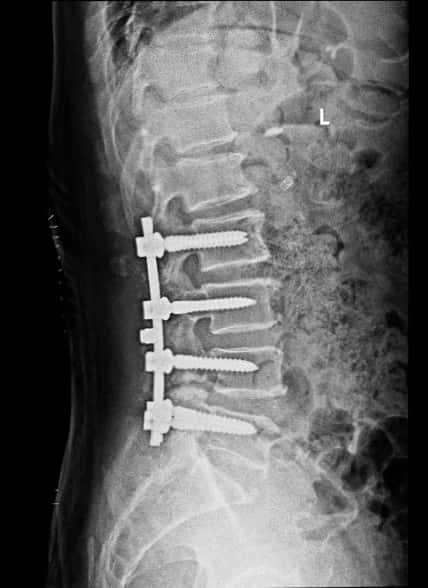

腰椎术后侧位片

腰椎侧位片子看腰4/5有轻度滑脱。

手术顺利,麻醉师功不可没!整个减压内固定的时间1小时23分钟,手术中出血约200毫升,出血回吸收122毫升。手术后右下肢疼痛消失,术后第四天下地行走,双下肢活动正常。术后两周一切平稳,没有出现高血压,心脏病相关的并发症。